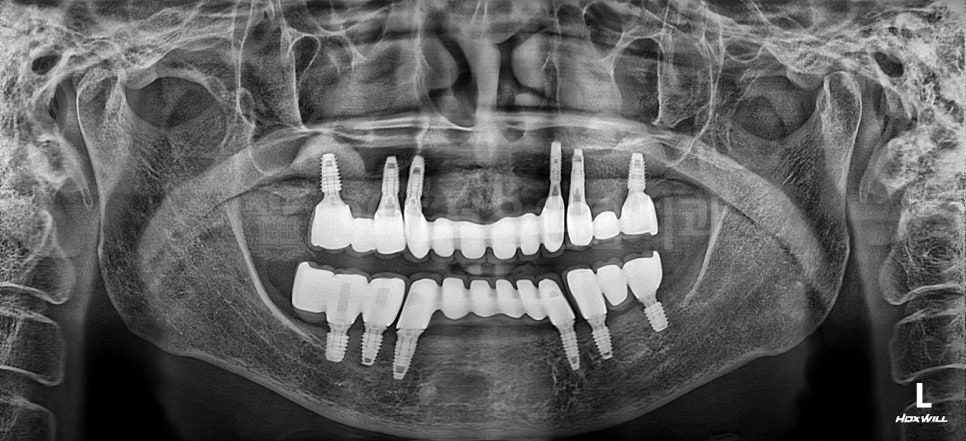

설명을 위한 예시자료입니다.

실제로 최근 70대 중반 여성 환자분도

장기간 골다공증 약을 복용 중이셨지만

저희 병원에서

전체임플란트를 진행하시고

현재 불편함 없이 잘 사용하고 계시며

정기검진을 꾸준히 받고 계십니다.